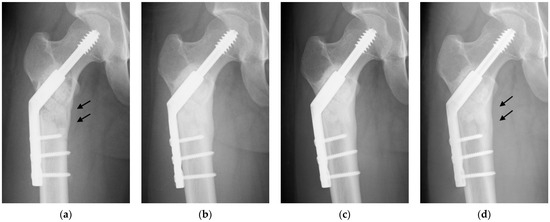

Figure 2. Radiographs of a 23-year-old simple bone cyst of the right proximal femur treated with UDPHAp [6]. (a) The UDPHAp implantation and internal fixation were shown on a radiograph 2 weeks postoperatively. A lytic change with cortical thinning of the medial bone cortex (arrows) was noted. Full weight bearing was allowed one day after surgery, and the patient returned to normal daily activities 2 months postoperatively; (b) moderate bone formation in UDPHAp was confirmed 7 months postoperatively; (c) the generation of medial cortical thinning was seen 13 months postoperatively; (d) UDPHAp resorption and bone marrow remodeling were observed 2 years and 6 months postoperatively. The decrease in medial cortical thickness was completely reversed (arrows).

2. Clinical Application to Bone Tumor Surgery

We retrospectively analyzed 44 patients who underwent intralesional resection and UDPHAp implantation for benign bone tumors between 2010 and 2015 [6]. Patients who were surgically treated for local recurrence were excluded. There were 30 males and 14 females with a mean age of 24 years (range, 8–72 years). The most common histologies are simple bone cyst, enchondroma, giant cell tumor of bone, and fibrous dysplasia. Adequate amounts of both block- and granule-type UDPHAp were implanted into bone defects after tumor resection in 24 patients, and only granule-type UDPHAp was implanted in 20 patients. We evaluated radiographic changes, clinical outcomes, and complications after UDPHAp implantation for the treatment of benign bone tumors. Regular postoperative radiographs were taken in the outpatient clinic every 3–6 months. Two orthopedic surgeons who were blinded to the clinical conditions assessed radiographic changes in the implanted UDPHAp according to Tamai’s staging [3], which is divided into five stages based on bone formation in the implanted UDPHAp. Implanted UDPHAp showed diffuse extensive sclerosis in all patients, and the outlines of granular and block-type UDPHAp became indistinct on radiographs at an average of 12 months after surgery, indicating excellent new bone formation within and around the implanted UDPHAp (Figure 2). The absorption of UDPHAp and marrow space remodeling were observed in 45% of patients at a mean of 17 months postoperatively and were significantly more common in younger patients (Table 1). Early diffuse sclerosis due to new bone formation is a significant indicator of good implant resorption and bone remodeling. All nine preoperative pathological fractures healed completely within 3 months after surgery. Preoperative cortical thinning was completely regenerated in 84% of patients at an average of 10 months after surgery. Gender, age, location in the long bone, pathological fracture, and the volume of the UDPHAp implanted did not show significant associations with the regeneration of cortical thickness. Delayed wound healing, postoperative infection, and allergic reactions related to implanted UDPHAp were not observed. A patient with a simple bone cyst and a preoperative pathological fracture of the proximal femur fell down the stairs and developed a fracture 9 months after implant removal. The patient underwent another internal fixation and showed good bone healing at the final follow-up.